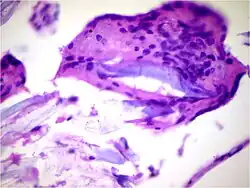

![]() |

Amoebiasis | Colonic biopsy showing trophozoite of Entamoeba Histolytica with ingested red blood cells. | Category: Histopathology of amoebiasis | Amoebiasis |